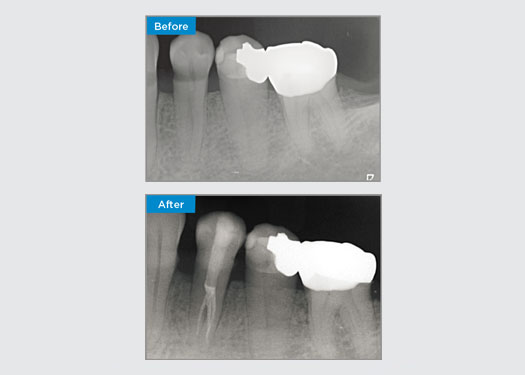

Этот пациент поступил со сломанной реставрацией на зубе 46 в дистально-окклюзионном отделе. Существующая реставрация зуба простиралась очень глубоко и близко к пульпарной камере. Учитывая большой размер реставрации, была высока вероятность того, что если мы просто заменим ее на другую прямую реставрацию, результат будет таким же, а реставрация сломается под действием окклюзионных нагрузок, которым подвергаются зуб и реставрация. Поэтому для этого зуба был рекомендован непрямой вариант реставрации. Поскольку мезиальная треть зуба была практически не затронута, и в ней сохранилась здоровая структура зуба, мы смогли сохранить ее и провести минимально инвазивное восстановление зуба с помощью непрямой реставрации с использованием системы CEREC.

Доктор Сахил Сони, Квинсленд, Австралия